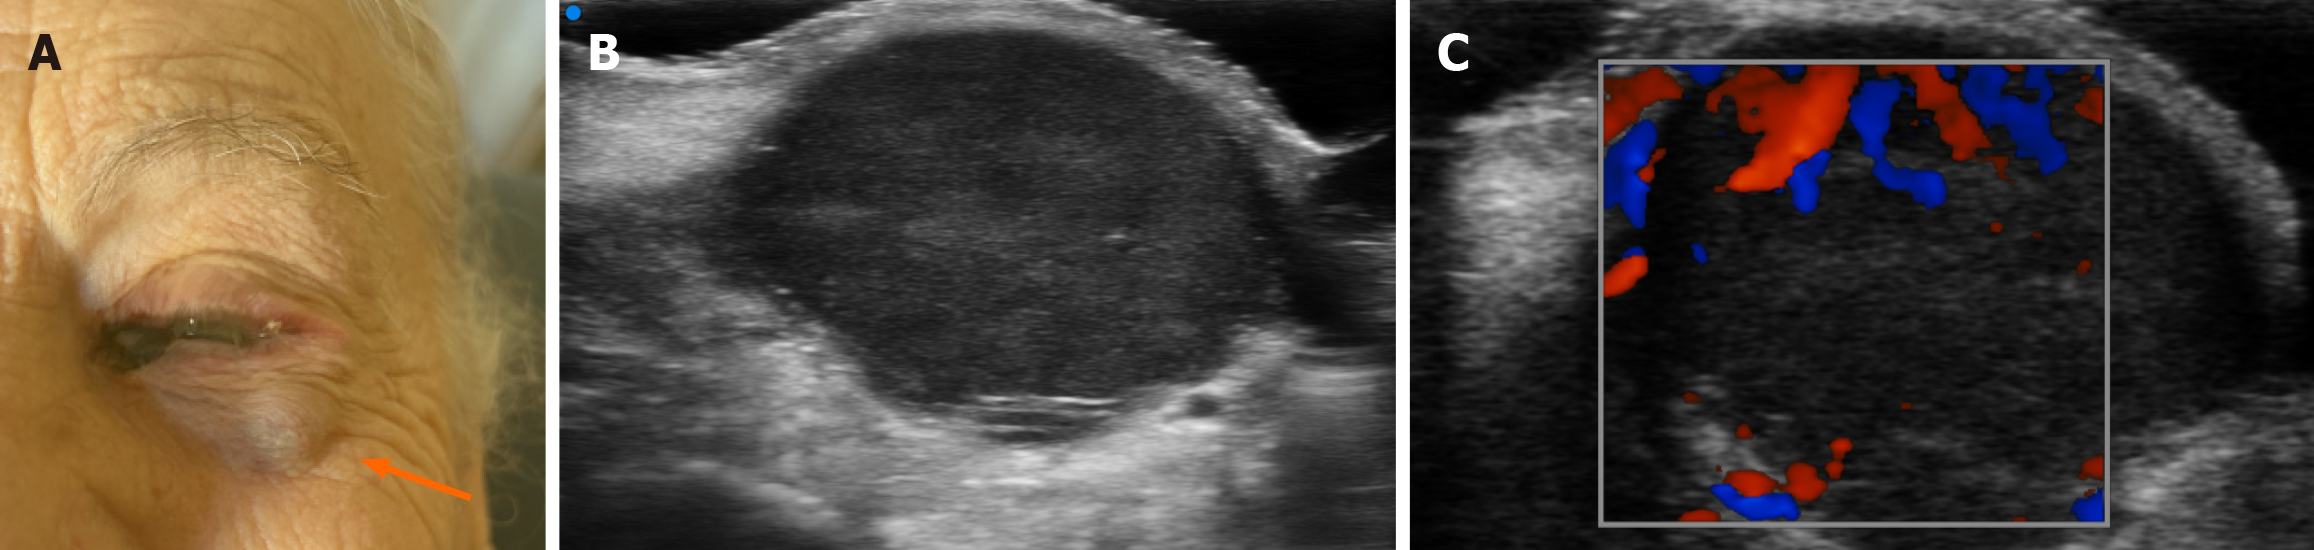

Figure 3 Multimodal assessment of suspected conjunctival melanoma recurrence.

A: Real-time clinical photograph showing pigmentation and visible subcutaneous nodule in the periocular region; B: Ultra-high-frequency ultrasound image (48 MHz) revealing epidermal thickening with disorganized echotexture and irregular margins; C: Corresponding Doppler image demonstrating increased vascular signals consistent with neovascularization.